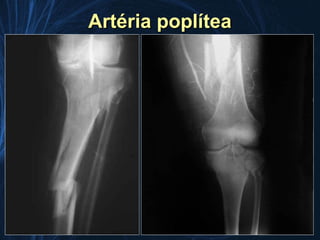

Artéria poplítea

• Anatomia frágil

• Colaterais sujeitos a

trombose

• Artéria terminal

• Maior índice de amputação

(diminuiu ao longo dos

anos)

• Luxação posterior do joelho

– Arteriografia mandatória